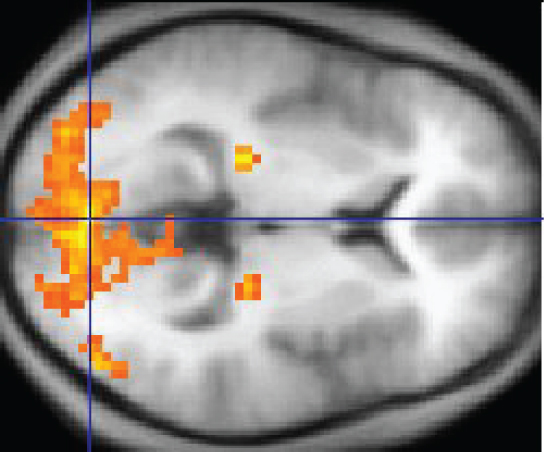

An easy way to see how much of the brain a person uses is to take measurements of brain activity while performing a task. An example of this kind of measurement is functional magnetic resonance imaging (fMRI), which generates a map of the most active areas and can be generated and presented in three dimensions (Figure 14.3.11). This procedure is different from the standard MRI technique because it is measuring changes in the tissue in time with an experimental condition or event.

The underlying assumption is that active nervous tissue will have greater blood flow. By having the subject perform a visual task, activity all over the brain can be measured. Consider this possible experiment: the subject is told to look at a screen with a black dot in the middle (a fixation point). A photograph of a face is projected on the screen away from the center. The subject has to look at the photograph and decipher what it is. The subject has been instructed to push a button if the photograph is of someone they recognize. The photograph might be of a celebrity, so the subject would press the button, or it might be of a random person unknown to the subject, so the subject would not press the button.

In this task, visual sensory areas would be active, integrating areas would be active, motor areas responsible for moving the eyes would be active, and motor areas for pressing the button with a finger would be active. Those areas are distributed all around the brain and the fMRI images would show activity in more than just 10 percent of the brain (some evidence suggests that about 80 percent of the brain is using energy—based on blood flow to the tissue—during well-defined tasks similar to the one suggested above). This task does not even include all of the functions the brain performs. There is no language response, the body is mostly lying still in the MRI machine, and it does not consider the autonomic functions that would be ongoing in the background.